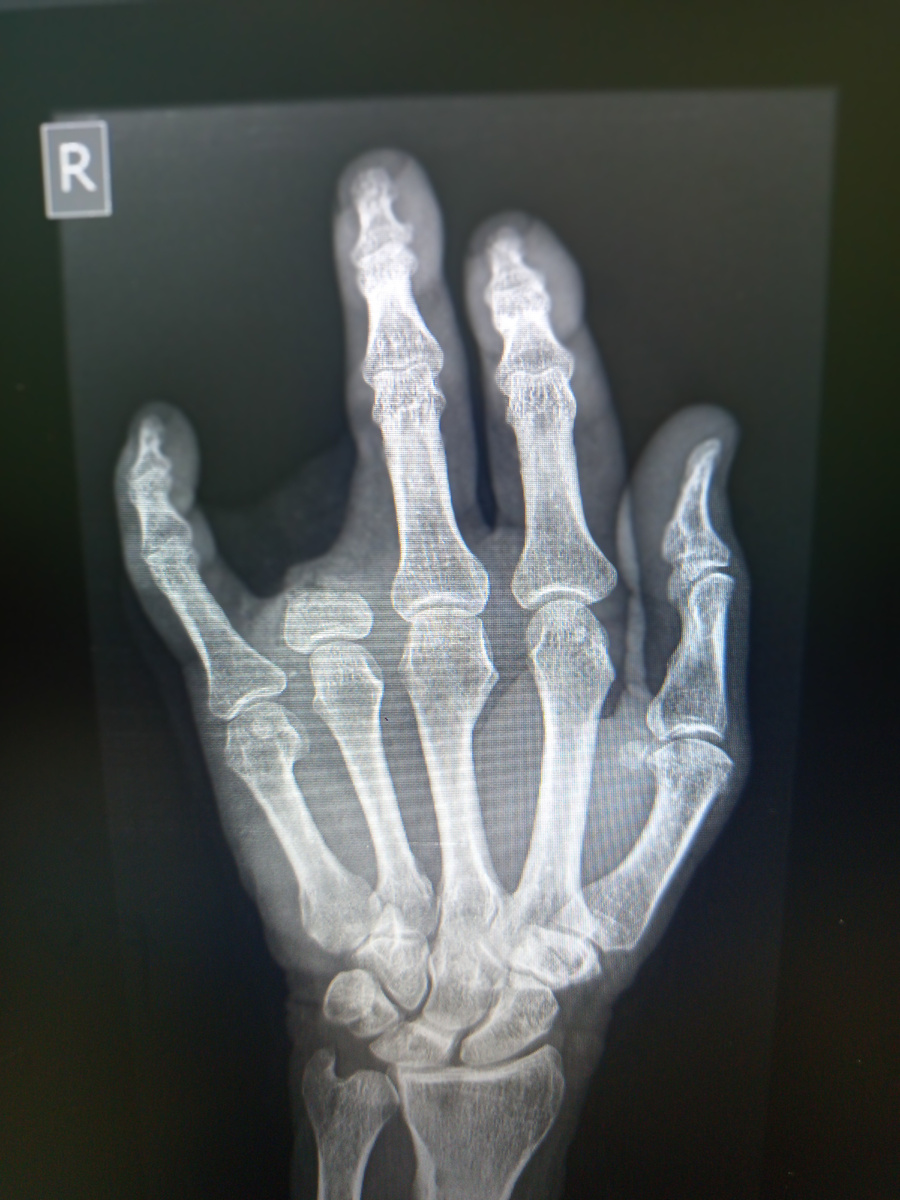

Мужчина 57 лет на снимок кисти пришел. Кисть замотана в платок.

Снимок неинформативен, но никто ему не будет убирать повязку в виде платка.

Сняла Борисовна , как есть.И через пять минут зазвонил телефон:

–Ага , угу, –говорит в трубку Борисовна. –Так а мы не обязаны раны разматывать, вы их сами размотайте, потом тогда на снимок присылайте! –положила она трубку.

–Кто там?

–Травматолог, не видно ему на снимке, что за травма.

Видимо , все сделали , потом на контроль прислали.